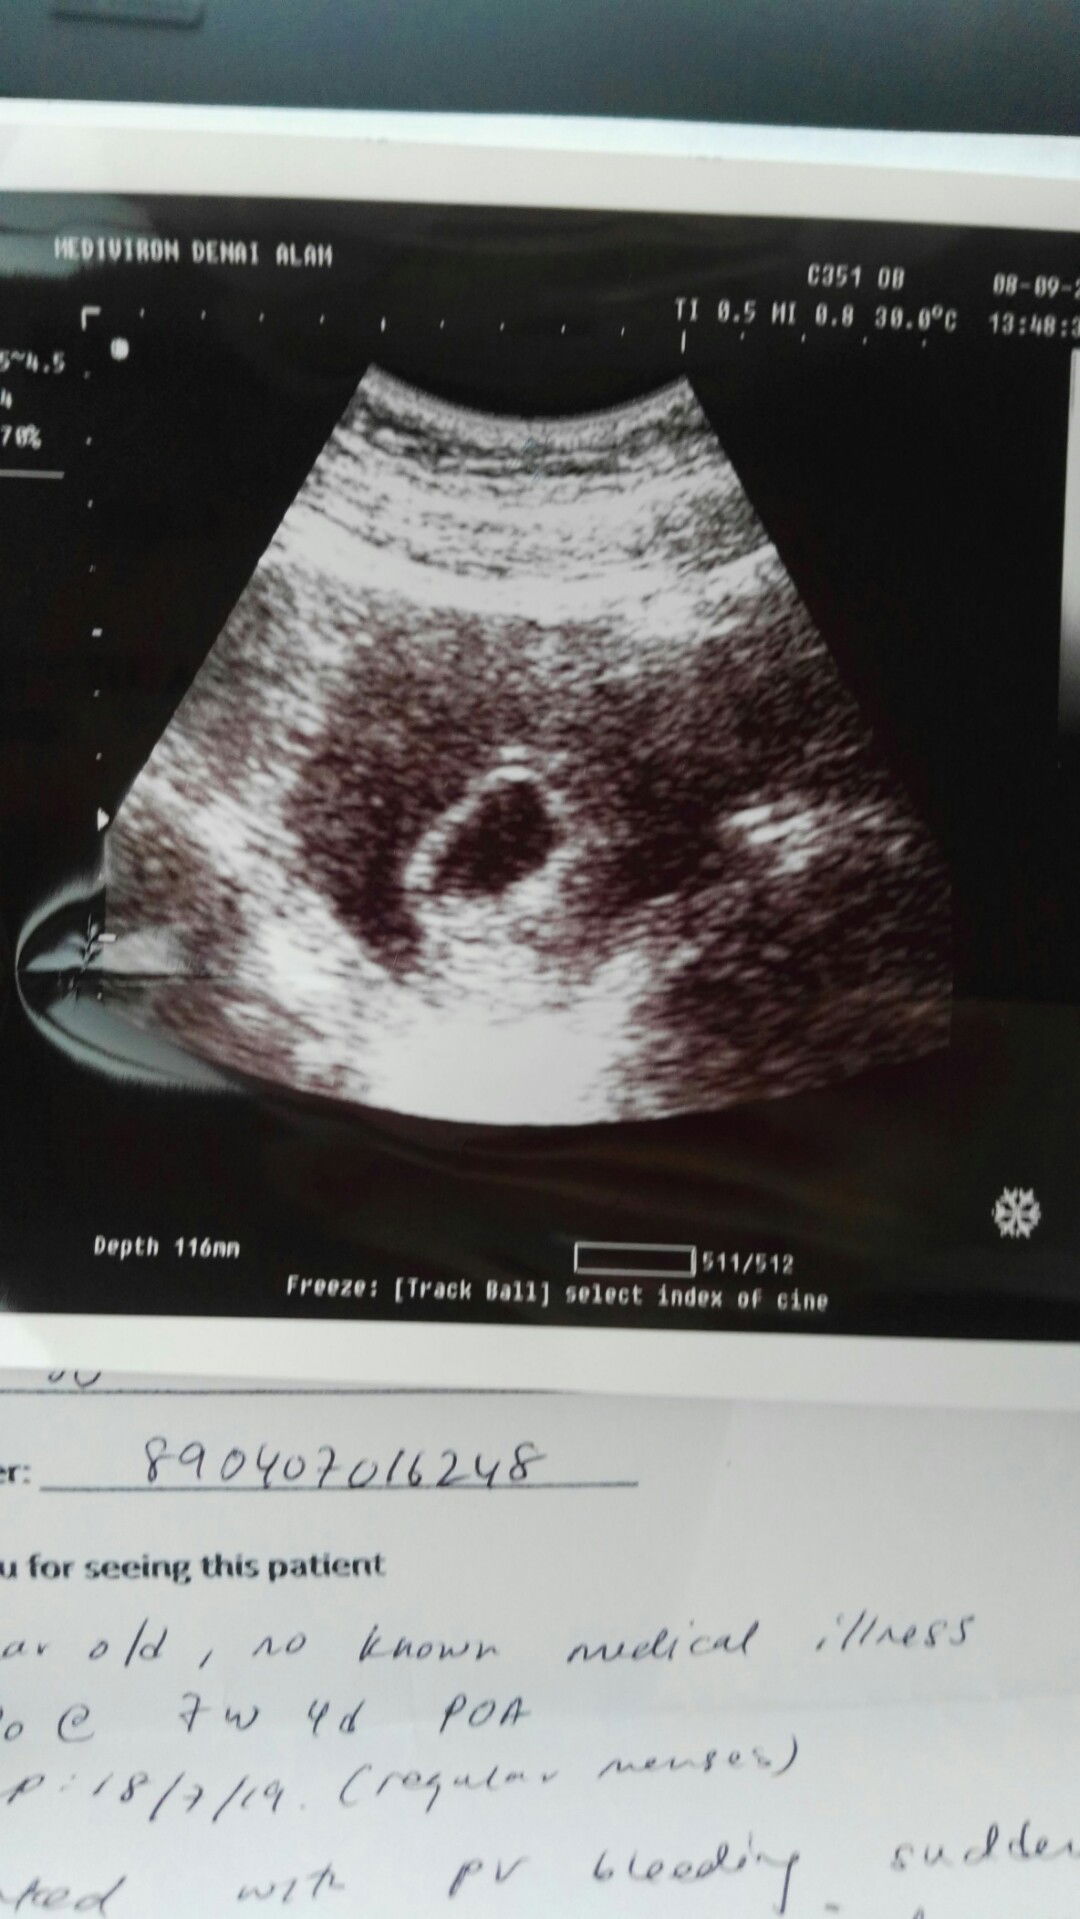

Subuh tadi buat test, Alhamdulillah positif. So dgn sabar tggu husband bangun tido nak pegi scan sbb dia keje mlm.. Dlm pukul 1:30 pm, kami singgah makan dkt KFC. Tgh tggu order, tetiba perut kejang tapi buat x tahu. Lepas siap makan, pegi toilet dan berlakunya bleeding. Masa tu, mmg dah cuak. Gugur ke? Period ke? Pegi klinik juga.. Doktor kata ada kantung, saiz dlm 6w. Kena pi hospital sbb bleeding. Pi hospital, doktor bagi kemungkinan yg sedih. Maybe kantong kosong tapi dia suruh pegi hospital dlm 2w lg utk pastikan sbb masih awal sgt. Klo dlm 2w ada bleeding ketul2 cepat2 pi hospital. Sekarang, mmg sedihlah sbb ni first pregnant. Tggu pun xlama mana pun sbb kahwin bulan 3 aritu tapi still rasa sedih. Ada apa2 pesan utk saya x?